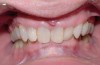

If the maxillary anterior teeth are positioned or inclined palatally, upon closure the lower teeth are going to first contact these teeth, which will force the mandible to shift to close into a retruded position. The objective is to try to identify this shift from primary contact to closure. This type of fence could potentially lead to shifting of the maxillary anterior teeth, breaking of the teeth, and/or muscular and jaw dysfunction as a result of posterior displacement of the mandible (Figures 2 through 5).

Figure 2

Figure 3

Figure 4

Figure 5